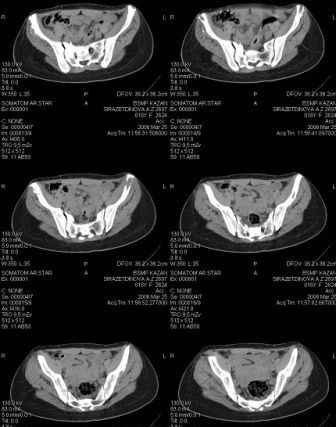

Предоставляю срезы. Если пациентку функционально ничего не беспокоит, стоит ли навязывать ей лечение.

Предварительный диагноз- посттравматическая вертикальная нестабильная деформация таза II степени, неправильно срастающийся перелом боковой

массы крестца справа, правой лонной и седалищной костей, застарелый разрыв лонного сочленения.

Для уточнения диагноза ниеобходимы обзорные рентгенограммы таза (прямая и inlet), Кт срезы на уровне переломов для определения степени сращения и решения вопроса о методе оперативного восстановления анатомии (делать ли остеотомию, низводить ли задние отделы), ни о какой "остеотомии выступающих отломков" тем более у девочки 18 лет речи быть не может.